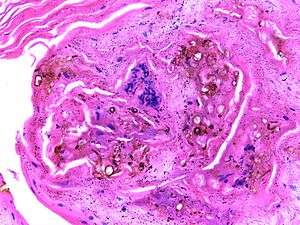

| Micrograph of chromoblastomycosis showing sclerotic bodies | |

On histology, chromoblastomycosis manifests as pigmented yeasts resembling "copper pennies". Special stains, such as periodic acid schiff and Gömöri methenamine silver, can be used to demonstrate the fungal organisms if needed.